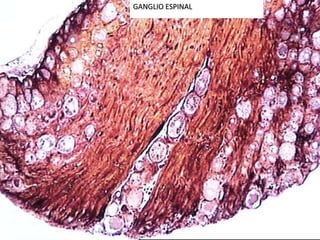

GANGLIO ESPINAL

Clasificación de lasneurogliasOligodendrogliasMacrogliasProtoplasmáticosSNCAstrocitosFibrososMicrogliasCélulas del epéndimoCélulas satélites o anficitos: Se localizan en los ganglios nerviosos.SNPCélulas de Schwann: Responsables de la formación de mielina en el SNP.Células de Müller: En la retina